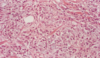

Breast - fibrotic stroma with compressed atrophic ducts and lobules

Dense connective tissue with dilated ducts and cyst formation